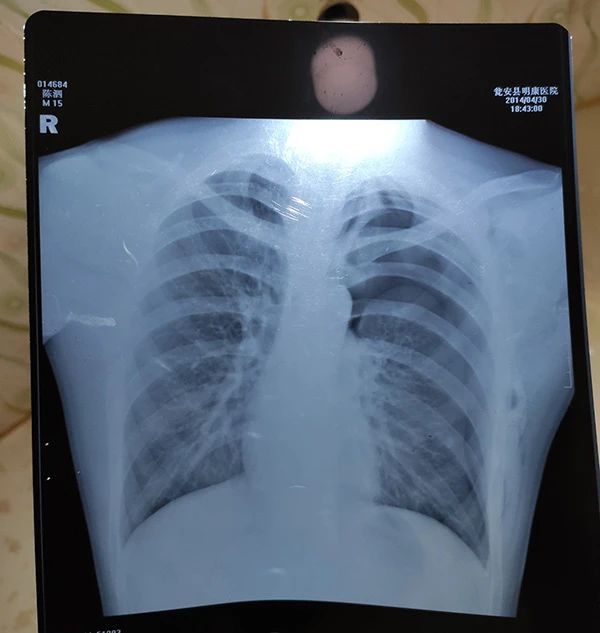

当晚的胸片报告显示左肺被压缩约75%,经县公安局法医鉴定为重伤二级。

案发当晚:陈泗翰的胸片